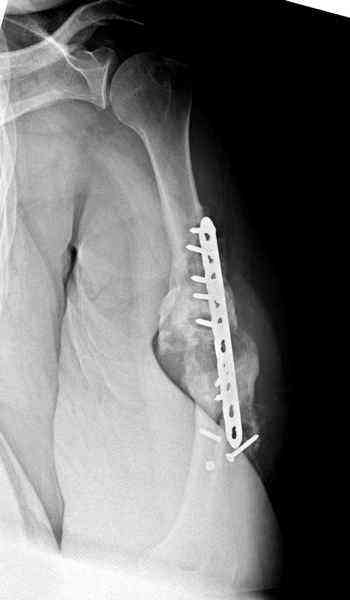

Хотя сам не стороннник применения более массивных

имплантов для плеча, но для этого случая сделали

исключение. На снимке 4А диаметр мягких ткани около 20 см, при весе больной более 135 кг, и также выступление Андрея Волны подстегнуло к применению более массивной 4.5 мм локинг пластины.

Биологические стимуляторы типа Synthes chronOS мы

применяем только для закрытия дефекта в закрытом

пространстве, например в тибиал плато, пилоне и

ацетабулярных переломах.

Несмотря на то, что компания рекомендует, что препарат является остеоиндуктивным, но мы считаем, что препарат надо применять для заполнения дефектов, потому что "indicated for use in bony voids or gaps that are not intrinsic to the stability of the bony structure.

chronOS is indicated for use treatment of bony defects created surgically or through traumatic injury".

А для стимулирования мы применили массу из состава:

OP1 с деминерализованной костью, добавив к ним еще

красную часть, приготовленную из крови больной.

Взятая перед операцией кровь в количестве 80 мл

провели через центрифугу и без сывороточной части

красную матрицу добавили к остальным.

С такой массой наверное ложный сустав "over killed", но надеюсь, что-то из них при такой фиксации окажет стимулирующее действие.